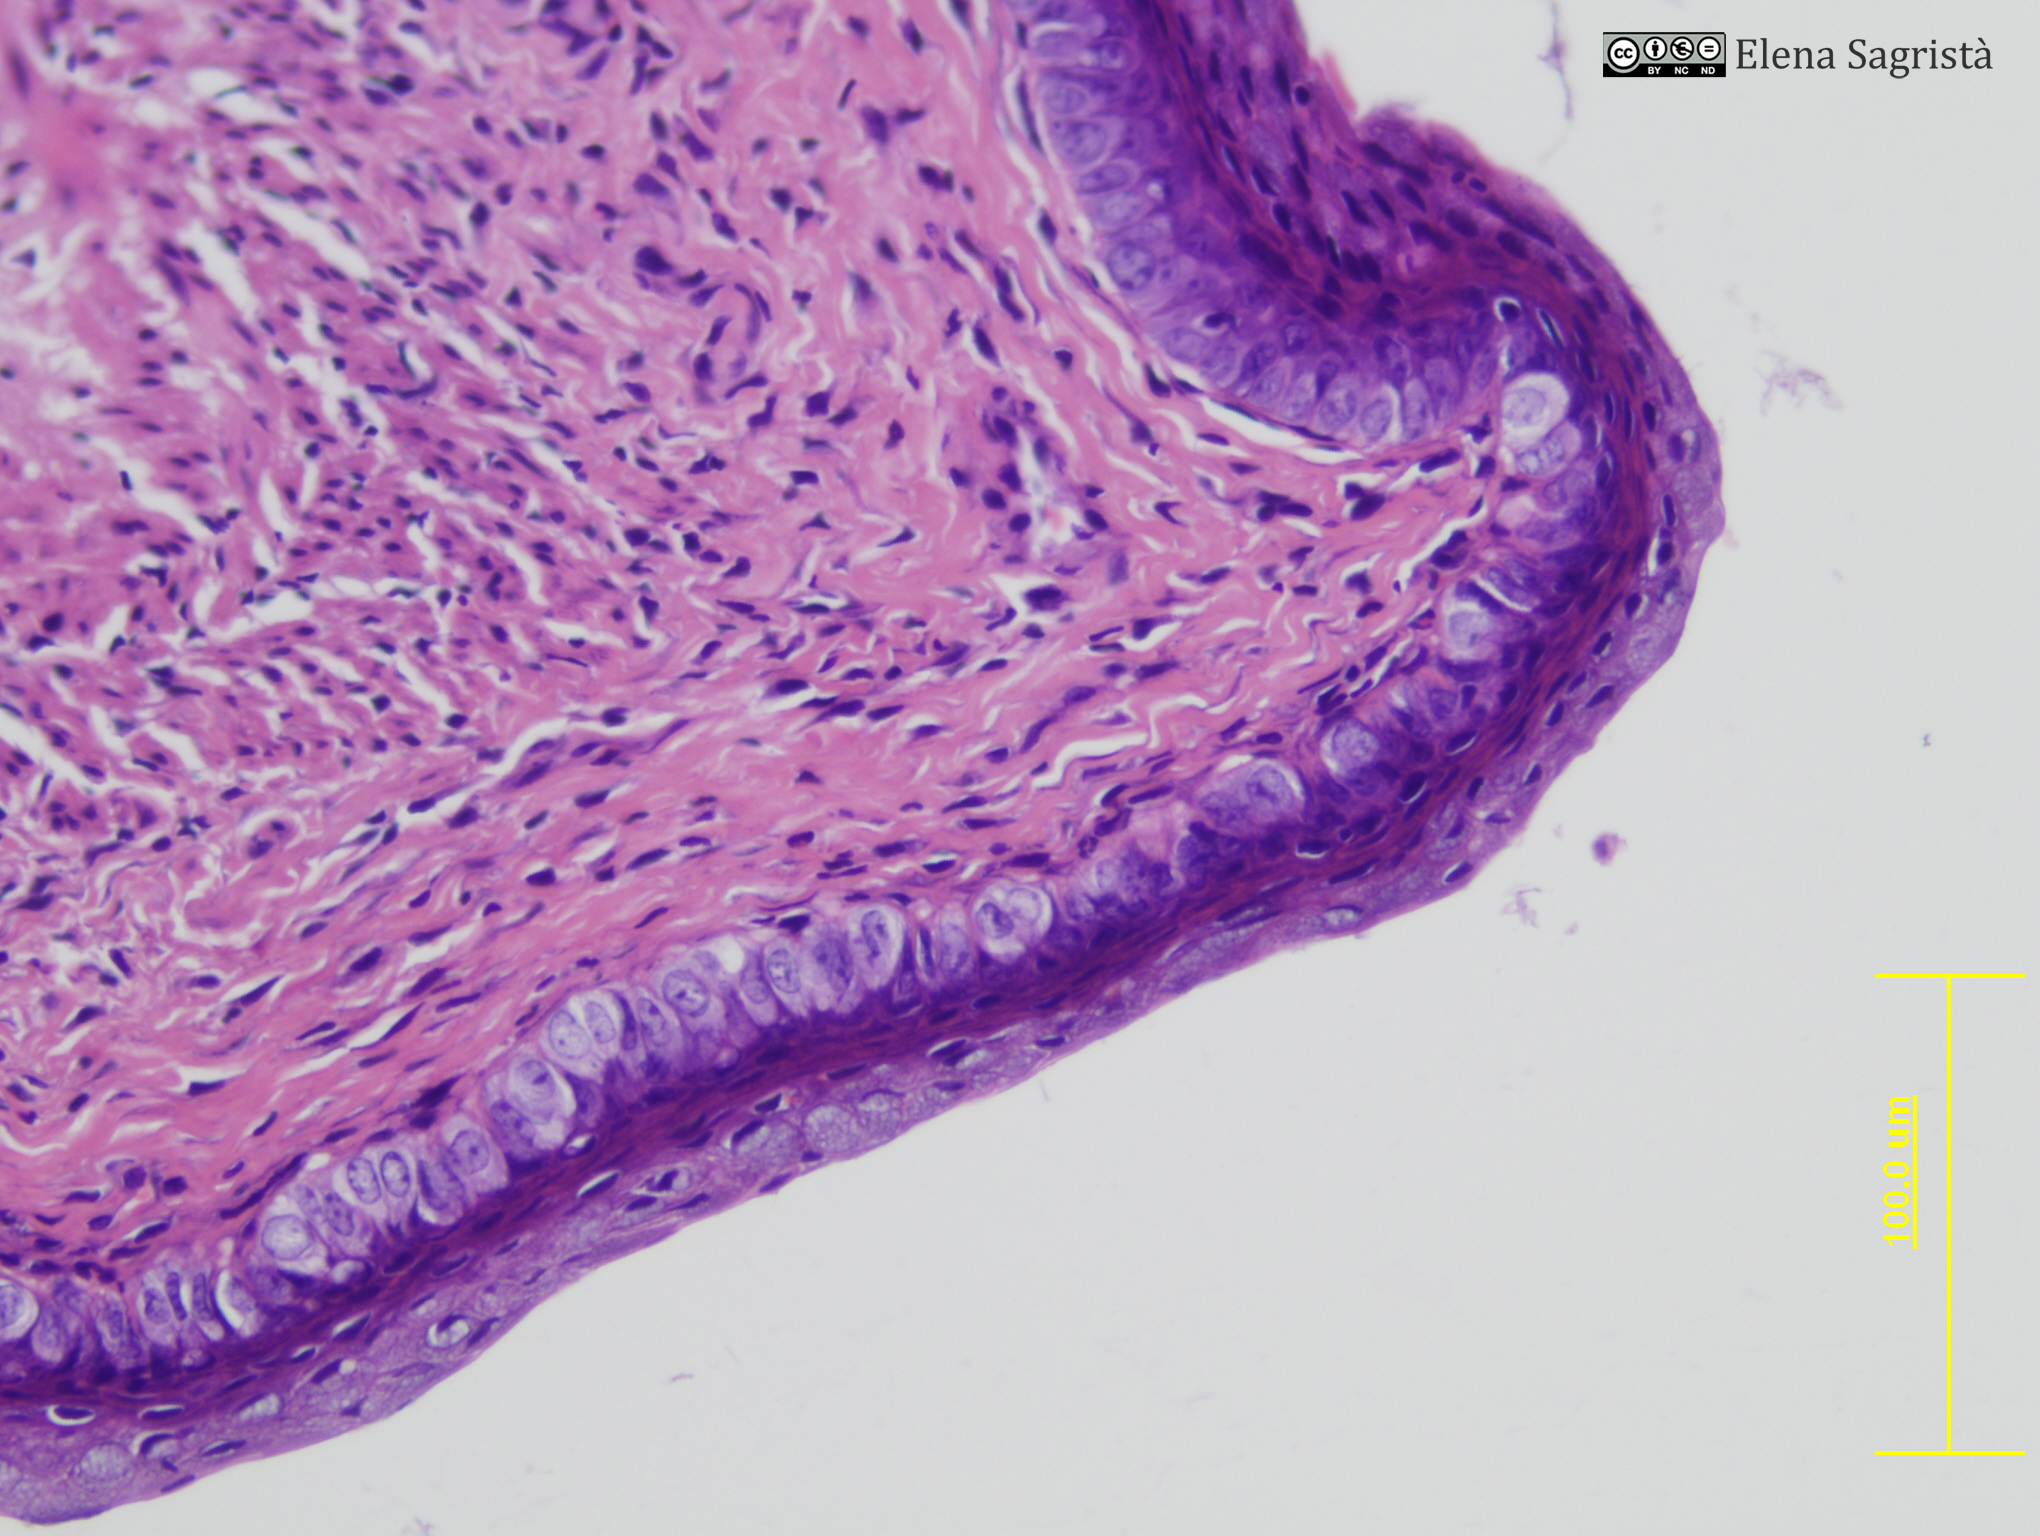

Imatges de preparacions histològiques d'Ovari i Aparell reproductor femení. Microscòpia òptica.